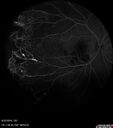

Coats' Disease -51 year old asymptomatic male398 views20/20 vision - had laser to non-perfusion because of proliferation.Jul 27, 2018